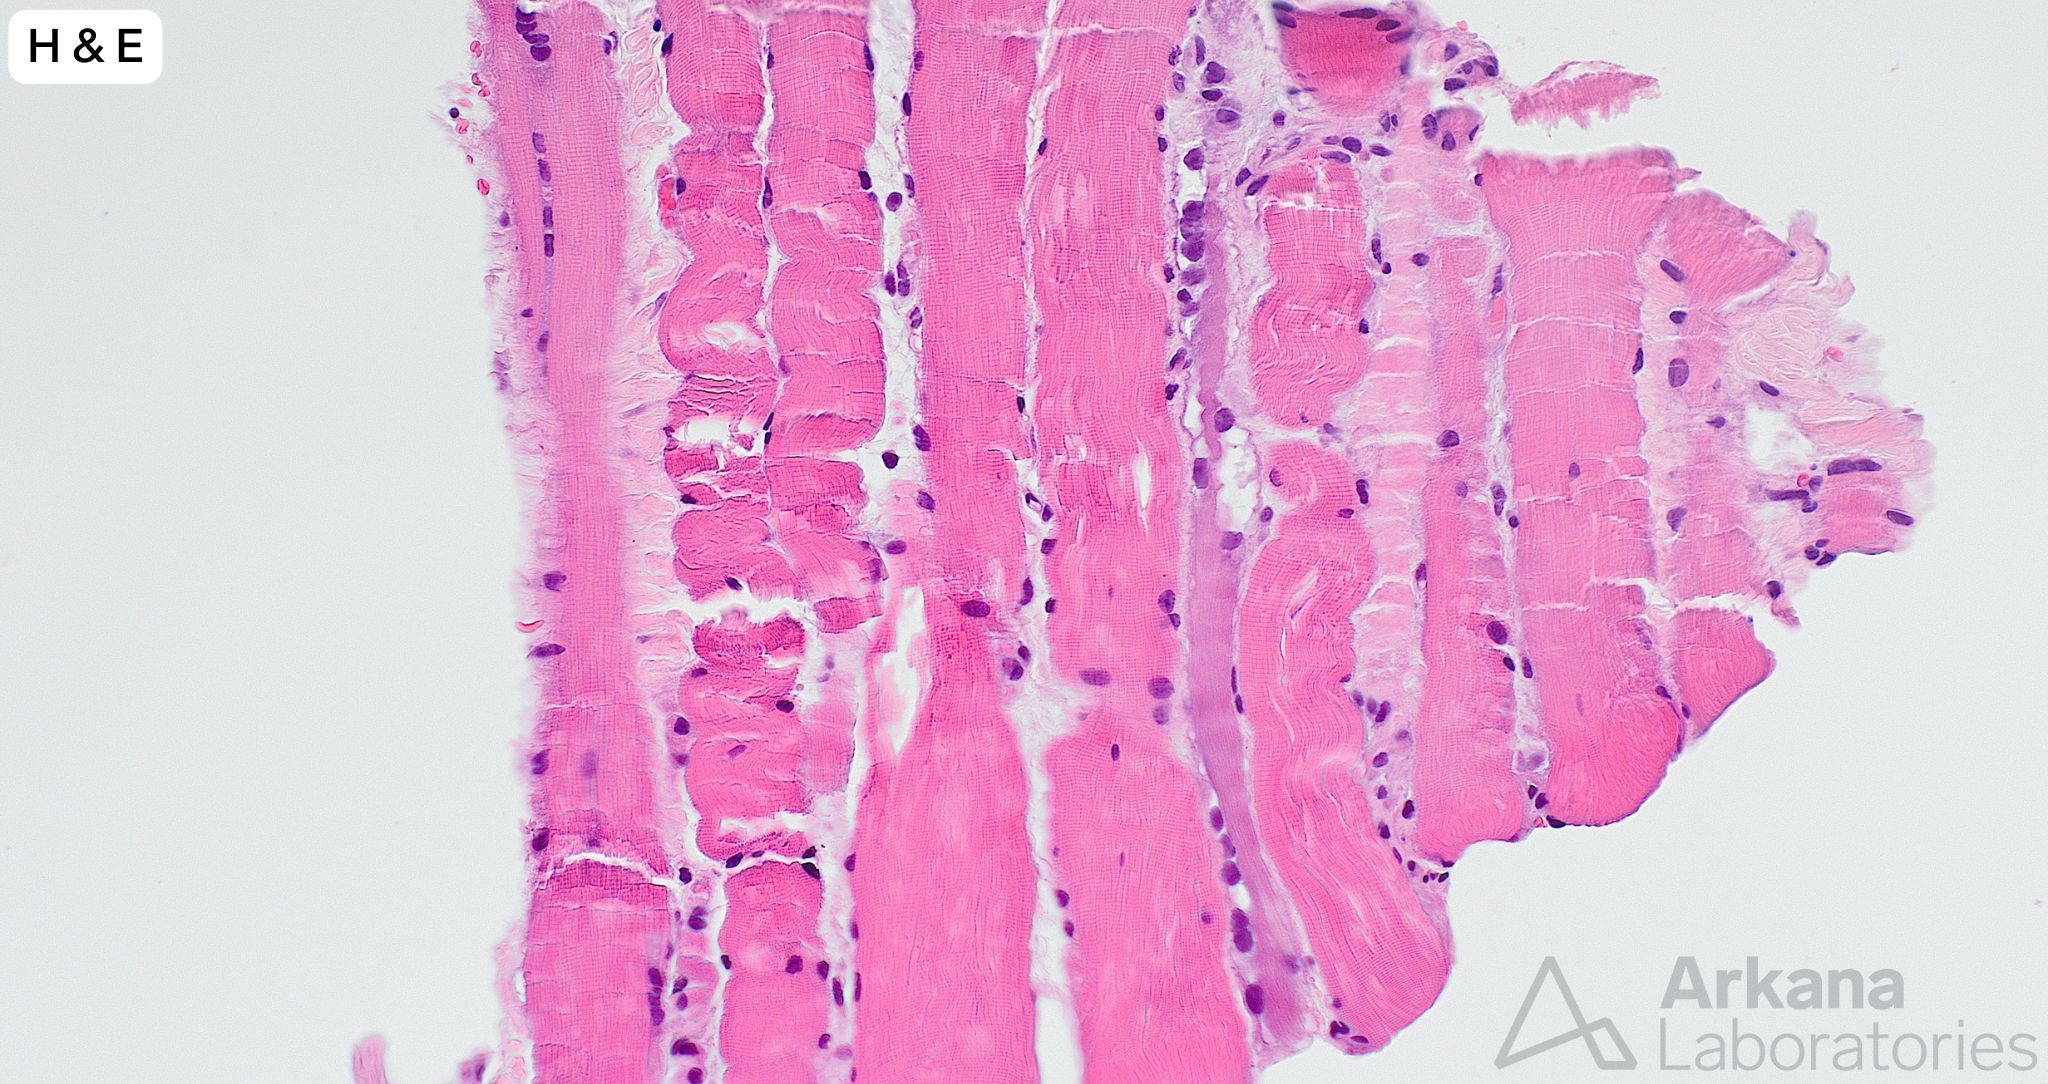

A needle core biopsy was performed of the left thigh. A minute fragment of fibrous tissue was present in tissue available for frozen section. The provided images (low and high magnification) show the total tissue available for evaluation in the formalin-fixed paraffin embedded tissue. The tiny fragment of glutaraldehyde-fixed tissue available for toluidine blue stained sections (image not provided) showed features similar to those seen in the FFPE tissue sections, and a few necrotic myofibers.

- The amount of tissue is extremely limited but shows a few regenerating and necrotic myofibers without associated chronic lymphoid inflammation. The overall changes are best categorized under the nonspecific descriptive umbrella term “necrotizing myopathy.”

- The pathologic alterations of necrotizing myopathy are not entirely specific as to etiology as they may be seen in a variety of contexts, including toxic myopathy (for example statin medication), immune-mediated necrotizing myopathy (SRP and HMGCR autoantibodies), partially treated acquired inflammatory myopathy, paraneoplastic myopathy, endocrine myopathy (thyroid), metabolic myopathy and infectious myopathy (viral).

- While significant information may be obtained from needle core biopsy samples, the “risk” of an issue of sampling compared to open biopsy is accentuated (i.e. processes involving muscle are frequently patchy in nature and morphologic features to enable a definitive pathologic diagnosis may be only partially represented or not present at all in the tissue submitted for evaluation).